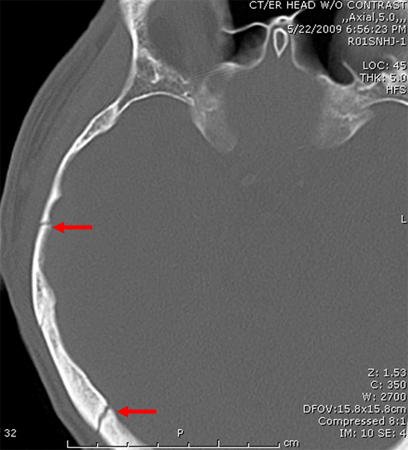

Uma história de trauma cranioencefálico (para detectar sangramento ou hematoma intracraniano)

[Figure caption and citation for the preceding image starts]: Fratura occipital se estendendo até o forame magno: risco de compressão do tronco encefálico por hematoma.Do acervo de aulas de Demetrios Demetriades, Division of Trauma and Surgical Intensive Care, LAC/USC Trauma Center, Keck School of Medicine da USC; usada com permissão [Citation ends].

[Figure caption and citation for the preceding image starts]: Fratura parietal linear sem depressãoDo acervo de aulas de Demetrios Demetriades, Division of Trauma and Surgical Intensive Care, LAC/USC Trauma Center, Keck School of Medicine da USC; usada com permissão [Citation ends].